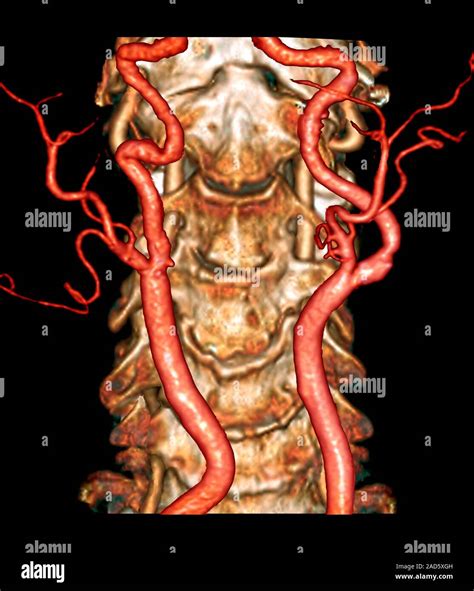

Understanding the importance of vascular health is crucial for maintaining overall well-being. One of the key components of this is the Carotid Artery Scan, a non-invasive procedure that provides valuable insights into the condition of the carotid arteries. These arteries, located on either side of the neck, supply blood to the brain, making their health vital for preventing strokes and other neurological issues.

A Carotid Artery Scan, also known as a carotid ultrasound, is a diagnostic test that uses sound waves to create images of the carotid arteries. This procedure helps healthcare providers detect any blockages, narrowing, or other abnormalities in the arteries that could lead to serious health issues. The scan is painless and typically takes about 20-30 minutes to complete.

The primary goal of a Carotid Artery Scan is to assess the risk of stroke. Strokes occur when blood flow to the brain is interrupted, often due to a blockage in the carotid arteries. By identifying these blockages early, healthcare providers can take preventive measures to reduce the risk of a stroke. Additionally, the scan can help monitor the progression of existing conditions and evaluate the effectiveness of treatments.